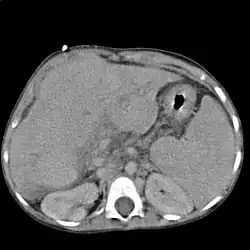

Elle est peu spécifique et sert essentiellement à détecter certaines causes rares ou des complications (cancer du foie).

L'échographie abdominale montre un parenchyme hépatique hétérogène et nodulaire, contours bosselés, avec une hypertrophie du segment I ou lobe caudé, des signes d'hypertension portale avec augmentation de la taille de la rate (splénomégalie)…

Le scanner et l'IRM sont meilleurs que l'échographie pour détecter un cancer du foie[2]. L'IRM est également fiable pour détecter certaines causes, notamment l'hémochromatose, par la mesure de la concentration en fer des tissus[15]. La fibroscopie œsogastrique peut retrouver des varices œsophagiennes, signe d'hypertension portale.